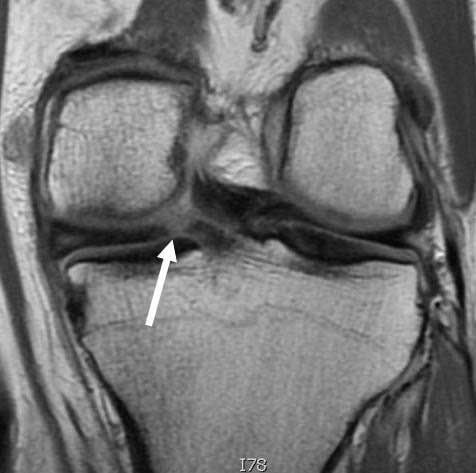

Great to be able to offer Meniscus transplant. #meniscus #knee https://t.co/g6geU8vXBA